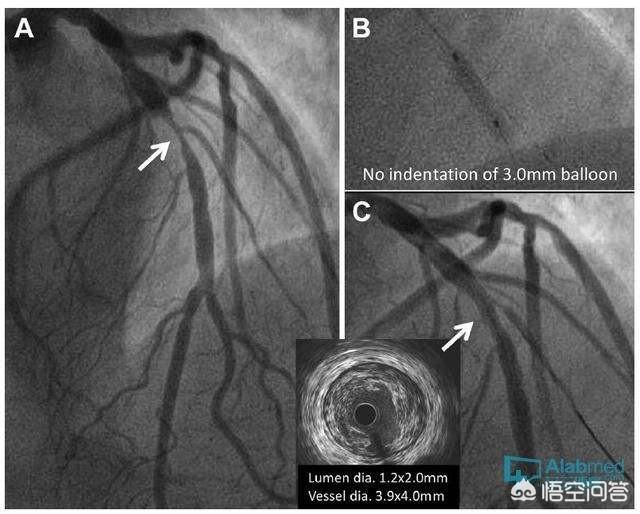

冠動脈造影または冠動脈CTAは、冠動脈狭窄の程度と範囲を調べ、狭窄の程度に応じてさらなる治療を行うために行われる。通常、冠動脈狭窄が80%以上で、明らかな虚血症状を伴う場合は、冠動脈内ステント植え込み術+薬物治療が勧められる。冠動脈の狭窄が50〜60%の場合は、まず薬物治療を行うことが推奨される。一般にバイパス・グラフトと呼ばれる冠動脈バイパス術は、冠動脈の病変が重症で多血管の場合にのみ必要である。